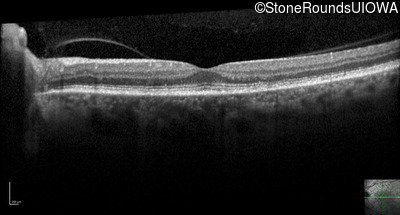

Optical Coherence Tomography - Right - 20/250

Exemplar / OCT Stack